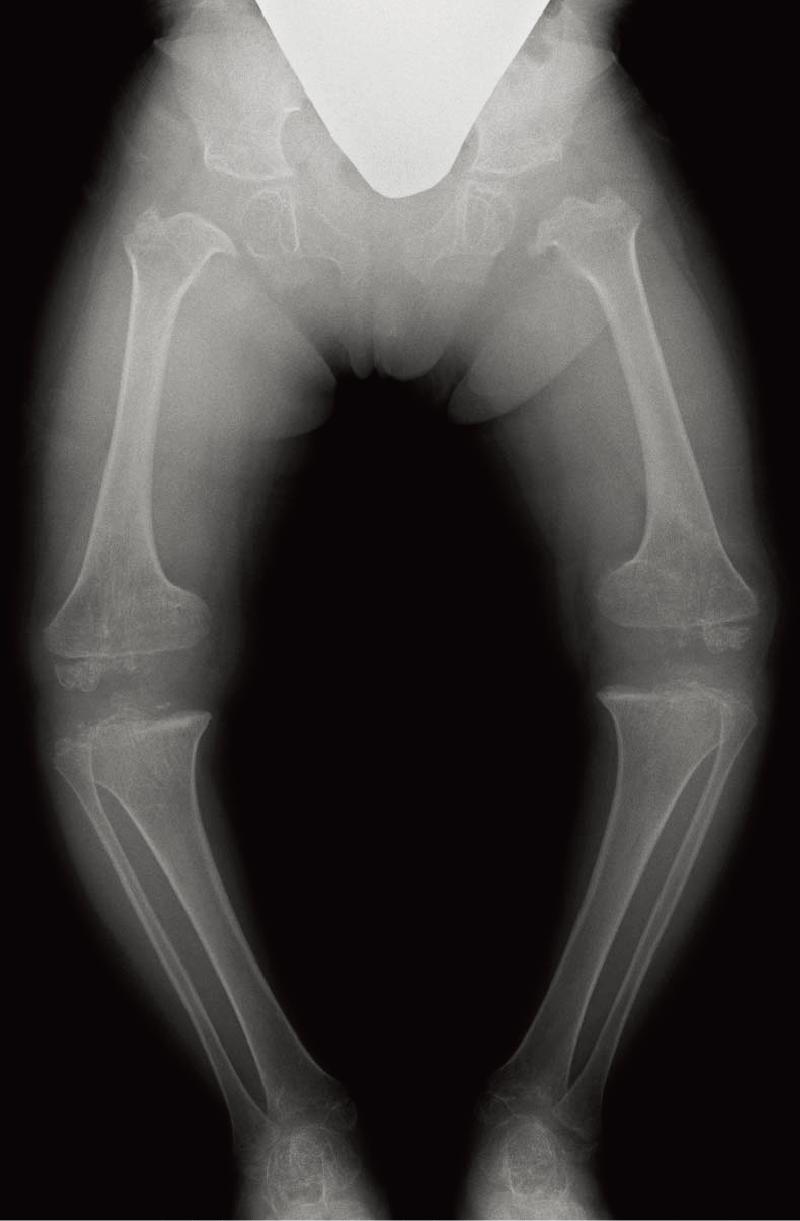

身長:低身長と著しい関節弛緩・脱臼が特徴である。

整形外科的臨床所見/特異顔貌および眼・耳などの合併症など:特異顔貌(卵型で平坦な顔、青色強膜、眼球突出など)を呈する。皮膚は柔らかく、筋緊張は低下する。進行性の脊柱変形があり(A)、下肢アライメント異常を呈することがある(B)。

B. 両下肢正面像(7歳、女):軽度の外反膝と骨端不整を認める。